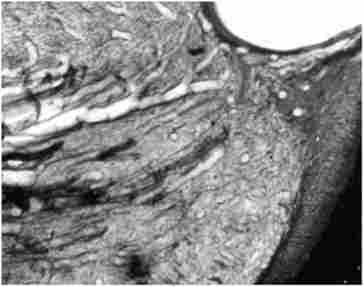

Запалення пульпи починається з гіперемії, освіти вогнищ дрібноклітинний інфільтрації з серозним, потім гнійним ексудатом. Змінюється кровотік, судини розширюються, спостерігається крайове стояння лейкоцитів (рис. 1.2). Накопичується ексудат, відтік якого через маленьке верхівковий отвір кореня зуба утруднений, підвищується тиск в порожнині зуба. Формуються периваскулярні інфільтрати. Одночасно знижується pH середовища до 4,8-5,2. Клінічно це проявляється нападами болю.

Гіперемія і набряк пульпи, крайове стояння лейкоцитів в судинах, 12 ч після травми. Забарвлення гематоксиліном і еозином. Мікрофото, х200

Мал. 1.2. Гіперемія і набряк пульпи, крайове стояння лейкоцитів в судинах, 12 ч після травми. Забарвлення гематоксиліном і еозином. Мікрофото, х200